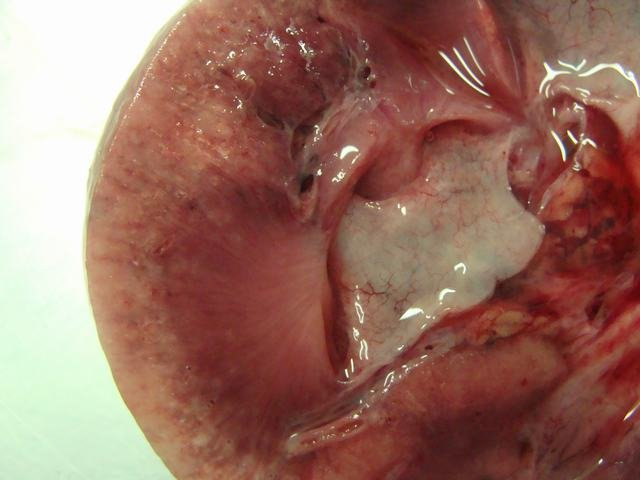

Content ยป Necrotic Kidney

necrotic kidney